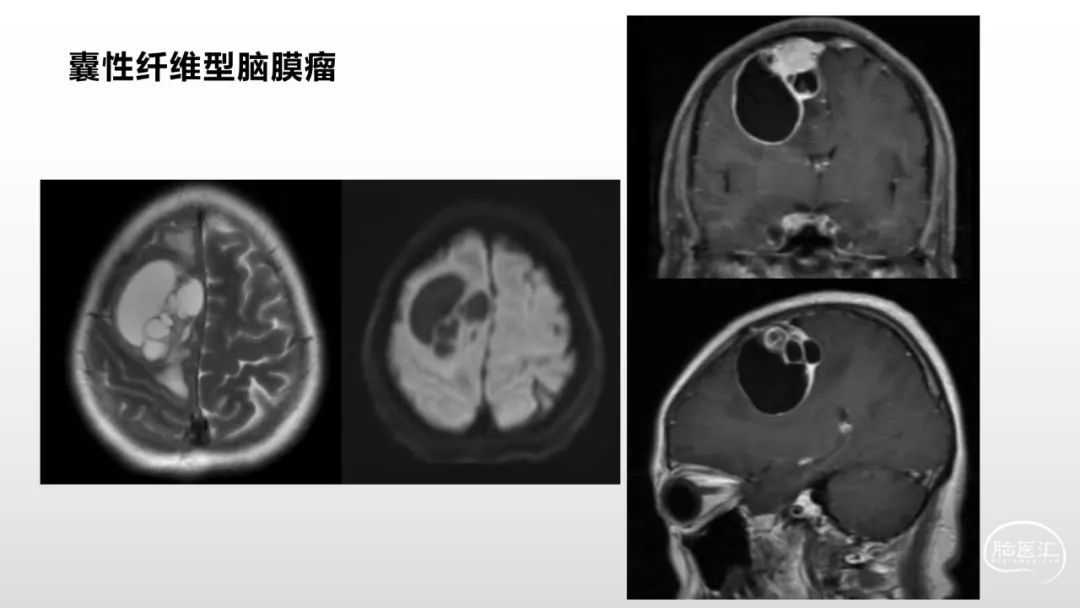

颅脑影像诊断基础知识讲座:脑膜病变

马洪舟

菏泽市立医院